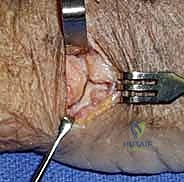

* *TECH FIG 1 • A. Brunner incision. The incision is made